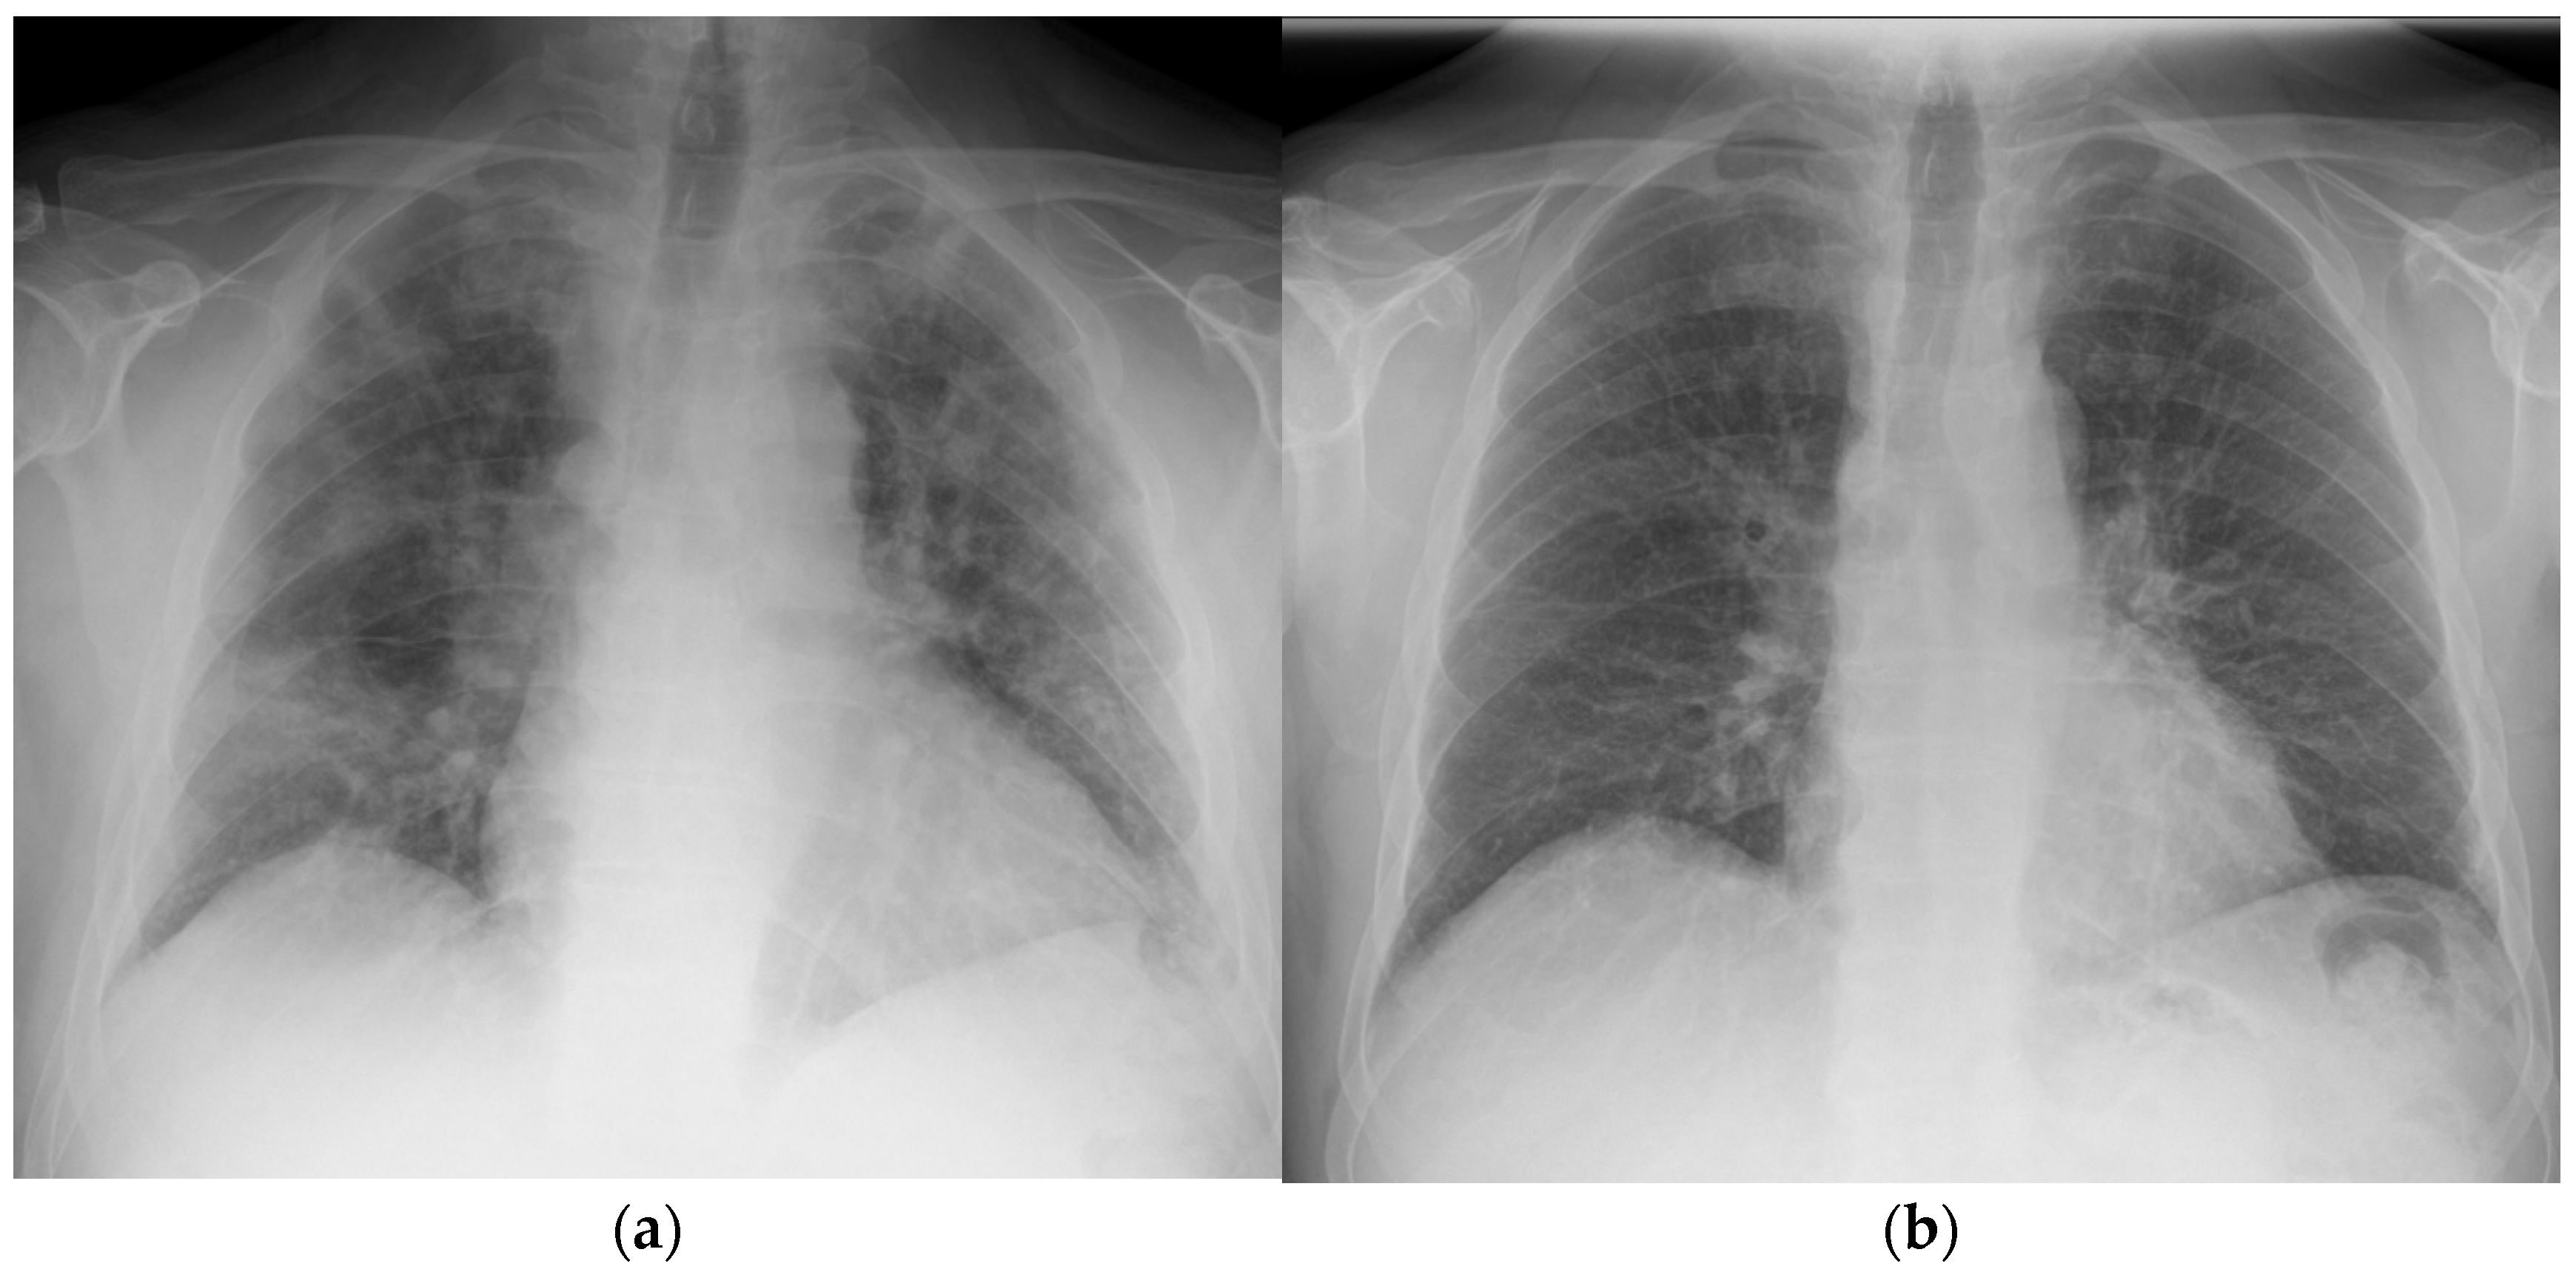

2.1. Patient 1

2.2. Patient 2

3.1. Patient 1

3.2. Patient 2